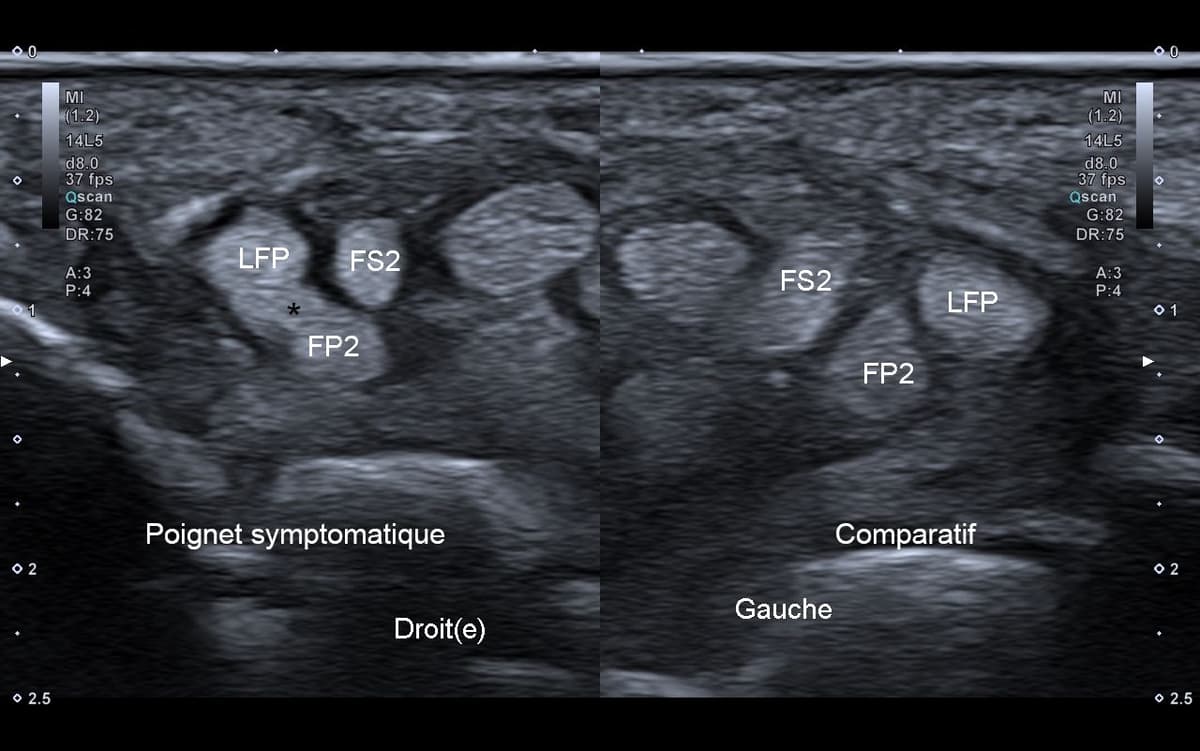

Syndrome de Linburg-Comstock

Le syndrome de Linburg-Comstock est une variante anatomique tendineuse entre le long fléchisseur du pouce et le fléchisseur profond de l'index.